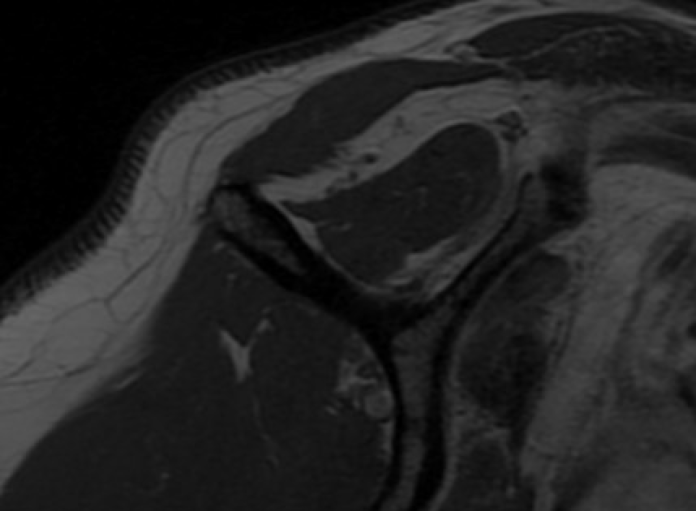

A 64 year old female presented with chronic right shoulder dysfunction and pain after an injury playing tennis in 2022, where she hit an overhead ball and felt a pop in her shoulder. She then had a recurrent injury in 2025 with a similar mechanism playing pickleball and was diagnosed with a rotator cuff tear. She had participated in PT and got some functionality back but remained weak, and then had a fall biking which further reduced the function of her shoulder. She complained of anterior shoulder pain and an inability to perform overhead activity due to weakness. Her exam revealed full active motion, but substantial weakness of belly press and lumbar lift-off. Passive external rotation was to 90 degrees. There was a palpable defect in the subscapularis. Plain radiographs were normal. MRI images are shown below.